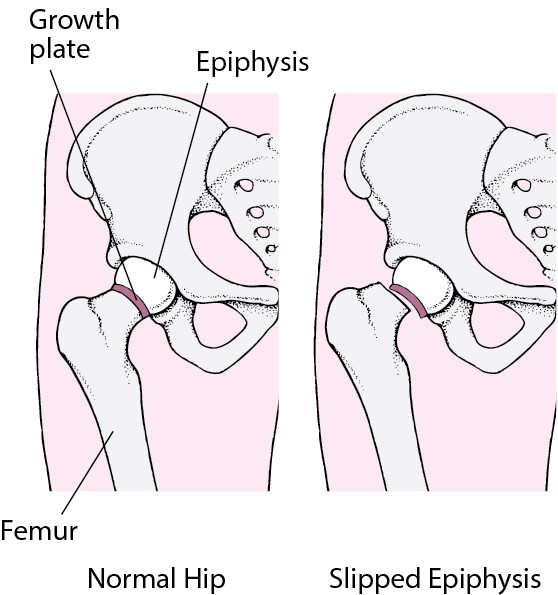

Slipped Capital Femoral Epiphysis | UW Emergency Radiology

femoral epiphysis slipped capital radiology scfe hip normal

Slipped capital femoral epiphysis (scfe). Slipped capital femoral epiphysis (scfe). Slipped capital femoral epiphysis radiology